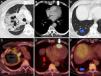

Se trata de un paciente de 64 años con clínica de síndrome constitucional que tras el ingreso en nuestro centro presenta un cuadro de neumonía obstructiva. Se practicó una TC en la que se observó una masa pulmonar en el lóbulo superior derecho con gran centro necrótico, una lesión cardíaca hipodensa de 20mm en ápex del ventrículo derecho compatible con metástasis y una imagen sugestiva de infarto pulmonar de localización subpleural en el lóbulo inferior derecho (fig. 1A-C).

A-C) TC de tórax tras la administración de contraste yodado intravenoso en ventanas de pulmón (A y C) y de mediastino (B). D-F) PET/TC tras la administración de 18F-FDG. Masa lobar superior derecha con amplias zonas de necrosis y cavitación (A) que mostraba elevado metabolismo glucídico en su periferia (D). Lesión en ápex del ventrículo derecho (B y E, flecha) sugestiva de metástasis cardíaca. Imagen nodular de base periférica con centro aéreo en lóbulo inferior derecho (C, flecha) sugestiva de infarto pulmonar. En la exploración PET/TC, esta lesión mostraba metabolismo (F, flecha) y se evidenciaba un émbolo arterial hipermetabólico en la rama aferente de dicho segmento (E, flecha gris) compatible con un embolismo tumoral.

Se realizó una fibrobroncoscopia con toma de muestras que filió la masa pulmonar como un carcinoma broncogénico de célula no pequeña. Para el estudio de extensión se llevó a cabo una PET/TC con 18F-FDG que demostró hipermetabolismo de la masa pulmonar, de la lesión cardíaca, de la zona de infarto pulmonar y en una arteria pulmonar del lóbulo inferior derecho (figs. 1D-F). La captación del infarto pulmonar sugirió que la causa del mismo fuera un embolismo tumoral.